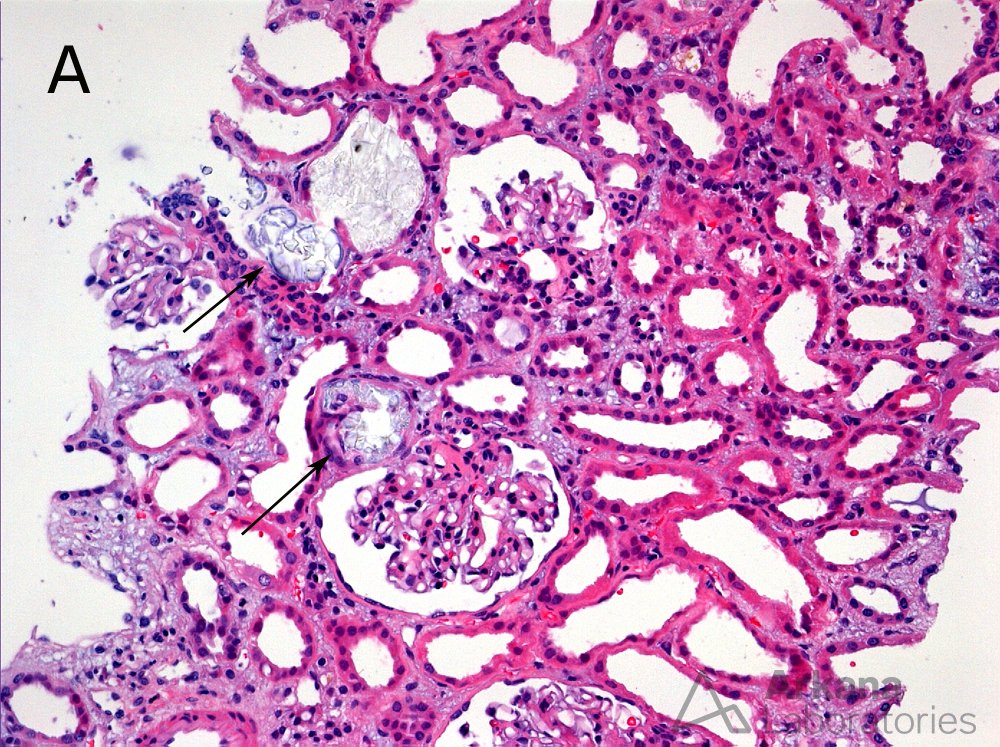

For today's #TeachingPoint, we'll review a 51 year old female with a history of SLE who was found to have acute renal failure. There was no evidence of glomerular proliferation by light microscopy but the biopsy did show (A) focal tubules with intraluminal and intracytoplasmic refractile crystals (arrows) (hematoxylin and eosin; original magnification × 100). (B) There are numerous intra-tubular birefringent crystals visible under polarized light (hematoxylin and eosin; original magnification × 50). These findings are consistent with kidney injury due to oxalate nephropathy. Known causes of oxalate nephropathy include primary hyperoxaluria, ethylene glycol intoxication, enteric hyperoxaluria (e.g. due to gastric bypass, chronic pancreatitis, small bowel resection, or malabsorption), exposure to the anesthetic agent methoxyflurane, vitamin B6 deficiency, and excessive ingestion of vitamin C or dietary substances rich in oxalic acid such as parsley, nuts, teas, and star fruit. The patient in the case shown here was found to be taking large daily doses of vitamin C.